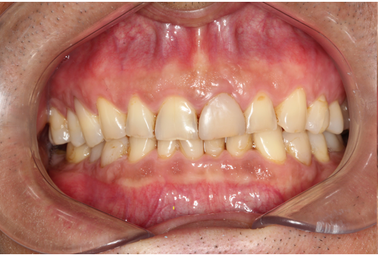

Mr NK, a 52-year-old male, presented with concerns of gradually shortening teeth and sensitivity to cold drinks. He also reported feeling self-conscious about his smile in photos. He is medically fit and has been using a night guard for his sleep-related grinding habit for the past year. Clinical examination revealed moderately worn dentition from erosion and attrition, along with mild crowding of the lower anterior incisors.

Intra-Oral Pictures (Before)

Our goal was to restore his smile as conservatively as possible, in line with his request to avoid full-crown preparations unless absolutely necessary. To achieve this, we planned a combination of veneers, veneerlays, and onlays, along with limited orthodontic intervention.

Key considerations:- Conservation of tooth structure: Partial orthodontic treatment was proposed to relieve anterior crowding, thereby reducing the amount of tooth reduction required.